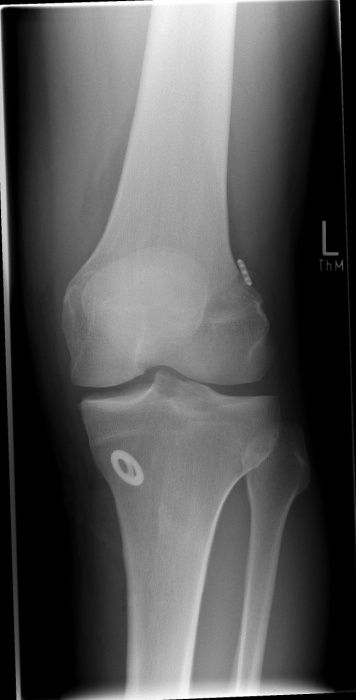

Üblicherweise fällt eine Instabilität im Gelenk durch eine orthopädische Untersuchung auf. Im weiteren diagnostischen Verlauf erfolgen Röntgenaufnahmen und eventuell eine Magnetresonanztomographie (MRT / Kernspin), um Begleitverletzungen am Knochen oder Verschleißerscheinungen im Gelenk zu erkennen.